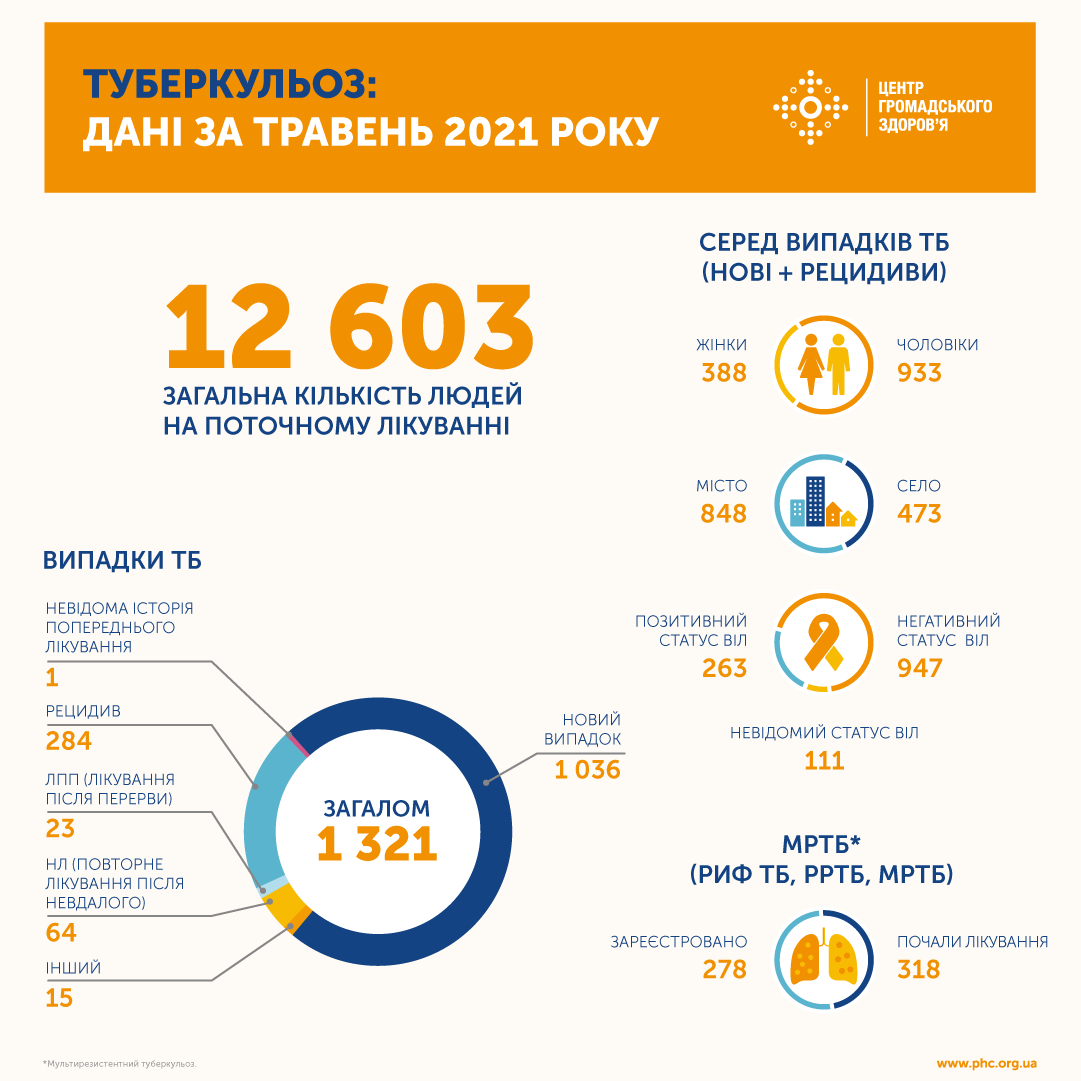

В мае 2021 года в Украине зарегистрировано 1321 случай туберкулеза. Такие данные приводит Центр общественного здоровья при Минздраве.

- 1036 новых случаев заболевания

- 284 пациентов с рецидивом

- 23 пациента, которые восстановили лечения после перерыва

- 64 пациента, которые начали повторное лечение после неудачного

- 15 других случаев

- 1 пациент с неизвестной историей предыдущего лечения

Всего в мае 2021 от туберкулеза лечились 12 603 человека.